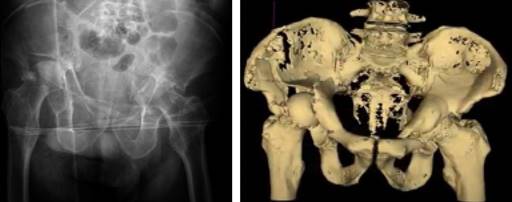

Clínicamente, el paciente presentaba un acortamiento de la extremidad inferior derecha en comparación con la contralateral, rotación externa y bloqueo articular a la realización del log roll test en ambas extremidades. Presentó impotencia funcional de ambas caderas. Dado el estado del paciente a su llegada a urgencias, no fue posible valorar el estado neurológico. No presentaba signos de heridas externas ni hematomas. Pulsos distales presentes a nivel pedio. Movilizaba extremidades superiores. Se realizó radiografía de tórax y anteroposterior de pelvis como parte del código de paciente politraumatizado, a la espera de completar estudio con tomografía computarizada (TC) abdomino-pélvico. En la radiografía de pelvis se diagnosticó luxación femoral de manera bilateral (Figura 1). Al paciente se le realizó una angiotomografía computarizada para descartar lesiones vasculares dada la inestabilidad hemodinámica que presentaba a su llegada. Se descartó lesión vascular tras la realización de la misma. En la reconstrucción 3D-TC de pelvis se objetivó fractura acetabular transversa bilateral según la clasificación de Letournel y fractura longitudinal del ala ilíaca derecha junto con protrusión intrapélvica de ambas cabezas femorales (Figura 1). Tras valoración inicial, se procedió a colocación de tracción transesquelética supracondílea femoral en ambas extremidades y retirar la cincha pélvica. El paciente estuvo ingresado en la unidad de reanimación hasta la cirugía, donde permaneció con las tracciones hasta la intervención.

Figura 1: Radiografía anteroposterior de pelvis inicial y reconstrucción 3D-TC donde se aprecia luxación bilateral central de fémur.